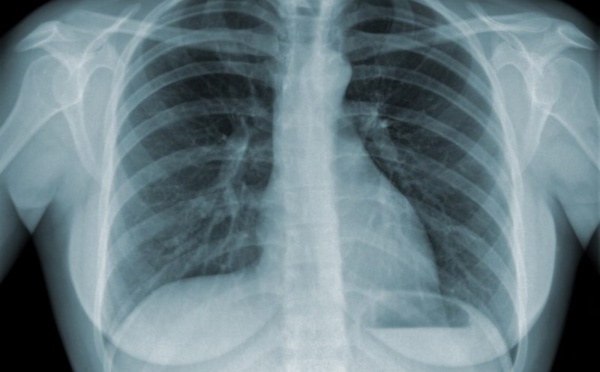

Journée mondiale de lutte contre la tuberculose: 13166 cas enregistrés en 2016 au Sénégal

La journée mondiale de lutte contre la tuberculose sera célébrée, ce vendredi. En prélude de ladite célébration, le Ministère de la Santé et de l’Action sociale communique sur la «maladie infectieuse la plus meurtrière au monde», selon l’Organisation Mondiale de la Santé (OMS).   La maladie infectieuse la plus meurtrière...